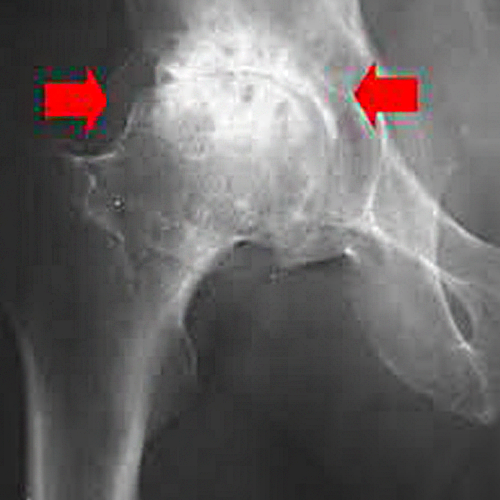

Диагностика ТБС рентгеном и асептический некроз: особенности лечения

Раздел: Снимки-откровения